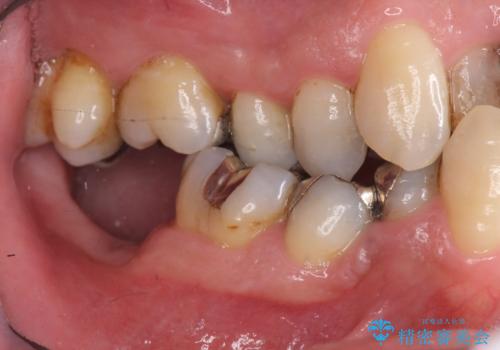

右下の奥歯も欠損しており、インプラント治療が必要な状態でした。

また、奥歯はインプラント治療を行い、矯正で下の前歯を後ろに下げるのに使用しています。

右下のインプラント治療は横浜桜木町歯科院長大元先生にお願いしています。